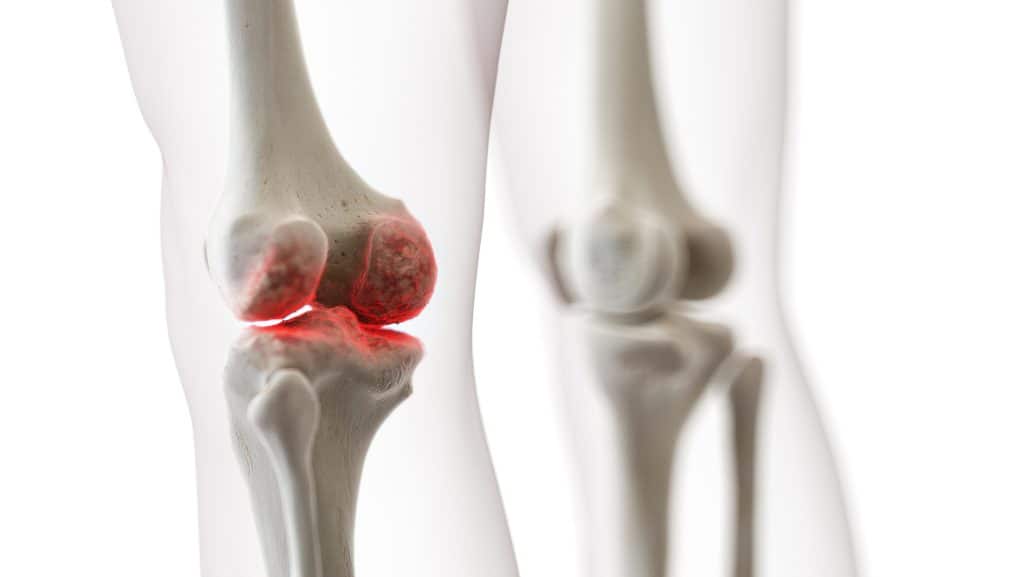

U vremenima kada mnogi od nas vode veoma ubrzane i pomalo stresne načine života, sve se to najviše odrazi na naše zdravlje. Jedno od većih slabosti na našem tijelu su zglobovi koji su najpodložniji boli i oslabljenju. Kako starimo tako hrskavica slabi i troši se u zglobovima, zbog čega dolazi do bolova u zglobovima. No, bol u zglobovima se može i prije pojaviti čak i u mlađoj dobi koji može biti zbog raznih razloga uzrokovan, od viška kilograma do preopterećenja. Bol u zglobovima osim zbog upale tj artritis može nastati i zbog ozljede. U oba dva slučajeva se može ovaj problem riješiti uz uzimanje Chondromaris kapsule koje će vam pomoći da se riješite boli što kraćem roku. Jednostavne su za koristiti te se mogu i putem interneta kupiti. Kroz ovaj članak ćemo vam reći kako funkcioniraju Chondromaris kapsule, kako se uzimaju te gdje se sve mogu one kupiti i treba li vam recept za njih.

Ono što čini Chondromaris kapsule tako efektivnim i popularnim za korištenje kod rješavanja boli u zglobovima jest što sadrži kvalitetne sastojke koje će vam pomoći da se riješite što prije boli i da povratite natrag snagu. Chondromaris kapsule mogu riješiti bol u svim zglobovima, što uključuje i ramena, koljena, prste, gležnjeve i kukove, te bilo da ste zadobili bol zbog ozljede ili je artritis uzrok, ovaj lijek će se pobrinuti da nestane što prije i bolje. Bol u zglobovima se može dogoditi osim zbog starosti, i zbog velikog opterećenja poput zbog fizičkog napornog posla ili ako se bavite profesionalno sportom, te isto tako i zbog prekomjerne tjelesne težine. Lijek se uzima na način da svaki dan u isto doba popijete jednu tabletu nakon jela i to uz čašu vode, te se držite toga narednih mjesec dana i trebali biste do tada primijetiti značajnu promjenu. Lijek mogu uzimati sve dobne skupine i to od 18 godina na dalje.